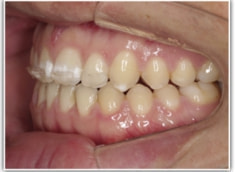

開咬(かいこう:オープンバイト)ケース

治療法:表の矯正(T21ブラケット)

(インプラントアンカーや外科矯正は行わず、エラスティックと機能訓練のみ)

治療後(2年2ヶ月後)